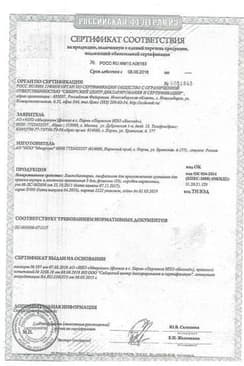

Сертификаты